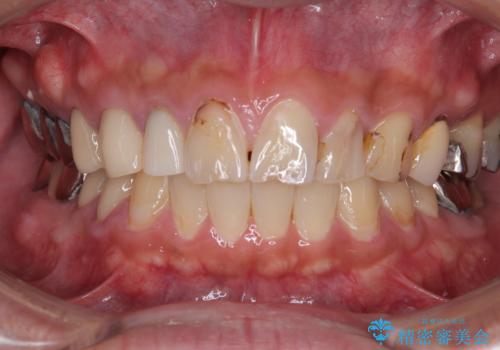

最新の症例

Latest cases